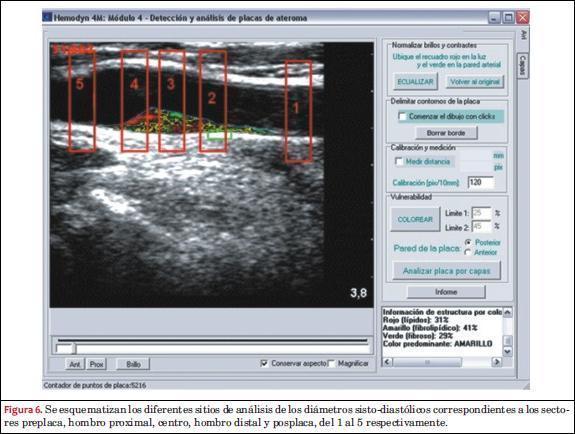

Con la imagen normalizada de la escala de grises, el software realiza automáticamente un mapeo en tres colores (rojo, amarillo y verde), dependiendo de su valor de la escala de niveles de grises. Los puntos de corte para el rojo, amarillo y verde fueron <50, entre 50-80 y >80, respectivamente(29). Este método determina “áreas rojas” dentro de la PAC, correlacionadas con un contenido hemorrágico o lipídico (ecogenicidad similar a la sangre); “áreas verdes”, correspondientes a una ecogenicidad similar a la adventicia representando contenido fibroso o calcificado; mientras que “áreas amarillas” abarcan el conjunto intermedio de la escala de grises entre las dos anteriores, que representan sectores con contenido fibrolipídico(13).

La clasificación de las PAC según su composición en tres grupos (hipoecogénica = lipídica; = isoecogénica = fibrolipídica; hiperecogénica = fibro/calcificada) se basa en la clasificación propuesta por Polak y colaboradores(53) y fue realizada automáticamente por el software y validada por los operadores. Se definió una PAC como fibrosa/calcificada (FC) o lipídica (L) cuando su estructura se componía de más de 50% por áreas hiperecoicas (“áreas verdes”) o menos de 50% por áreas hipoecoicas (“áreas rojas”), respectivamente. A su vez, se definió como placa fibrolipídica (FL) cuando ninguno de los componentes de las escalas de grises superó el 50%. En la figura 5 se puede observar un ejemplo de cada tipo de PAC a partir del mapeo de colores aportado por el software. Todas las imágenes fueron calibradas de manera protocolizada y estandarizada para permitir la comparación entre las PAC y reducir al mínimo las diferencias metodológicas.

Análisis de la distensibilidad arterial en el eje longitudinal de PAC y carótidas control

Como se ilustra en la figura 6, para cada arteria carótida con placa de ateroma, independientemente de su contenido, se establecieron cinco sectores de análisis de aproximadamente 3 mm, definidos como preplaca (sector 1), hombro proximal (sector 2), centro (sector 3), hombro distal (sector 4) y posplaca (sector 5). El mismo procedimiento de análisis fue llevado a cabo en las arterias control (G2) y los sitios analizados fueron los correlativos a los sectores estudiados en el G1.